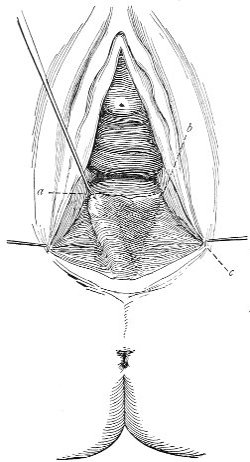

Slight Median laceration of the Perineum.—In this injury the tear takes place through the fourchette. Posteriorly it may extend as far as the sphincter ani muscle. Upward it may extend for an inch up the posterior vaginal wall. The appearance of this tear is shown in Fig. 33. It will be noted that, as this tear takes place in the median line, none of the muscles that support the perineum are involved, nor are the planes of fascia injured. The perineum is slightly split, and the insertions and origins of the muscles and the fascia are slightly separated. The supporting structures of the perineum and the pelvic floor are, however, uninjured.

Fig. 33.—Recent slight median laceration of the perineum: sutures introduced.

If this tear is detected after labor, it should be closed by the immediate operation. A slight tear involving chiefly the cutaneous aspect of the perineum should be closed by three or four sutures introduced from the outside, as in Fig. 33. The needle should be introduced about a quarter of an inch from the edge of the wound. It should not be passed parallel with the plane of the lacerated surface, but should be swept outward and then inward toward the 68 angle at the bottom of the tear (Fig. 34). It may either emerge at the angle and be re-introduced, or it may be passed directly through to the skin-margin on the opposite side of the wound. If the suture is passed in this way, there will be perfect apposition throughout the whole surface of laceration. If the sutures are improperly passed, there may result only apposition of the skin-edges.

Fig. 34.—Diagram representing the correct and the incorrect method of passing the suture for closure of slight perineal laceration.

If the laceration extends up the posterior vaginal wall, two sets of sutures must be introduced—one on the vaginal aspect of the tear, and one on the skin aspect (Fig. 35).